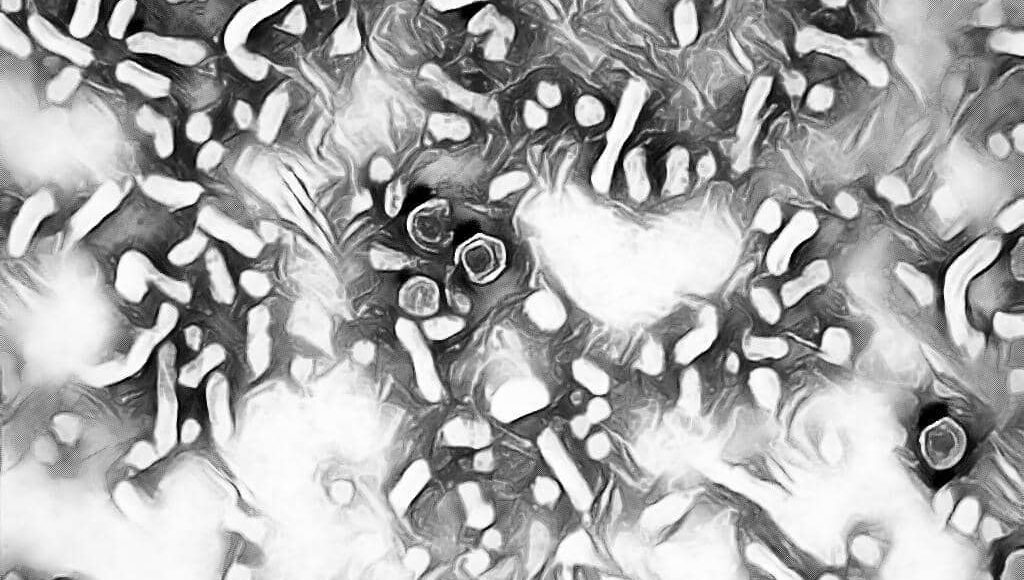

What is the Morphology of Hepatitis B Virus ?

[wp-svg-icons icon=”point-right” wrap=”i”]Â HBV is a complex 42 nm double-shelled particle consist of an outer envelope & an inner core.

[wp-svg-icons icon=”point-right” wrap=”i”]Â HBV is assigned to a separate family Hepadnaviridae.

[wp-svg-icons icon=”point-right” wrap=”i”]Â The outer surface or envelope of virus contains hepatitis B surface antigen (HBsAg).

[wp-svg-icons icon=”point-right” wrap=”i”]Â The core of the virus consists of an icosahedral 27nm nucleocapsid, which contains Hepatitis B core antigen (HBcAg).

[wp-svg-icons icon=”point-right” wrap=”i”]Â Inside the core is the genome, a circular dsDNA & a DNA polymerase.

[wp-svg-icons icon=”point-right” wrap=”i”]Â HBV, antigenically, have been divided into 3 types of particles as:-

- HBsAg – Hepatitis B Surface Antigen a.k.a. Australia antigen.

- HBcAg – Hepatitis B core Antigen a.k.a. Core antigen.

- HBeAg – Hepatitis B early Antigen a.k.a. Early antigen.